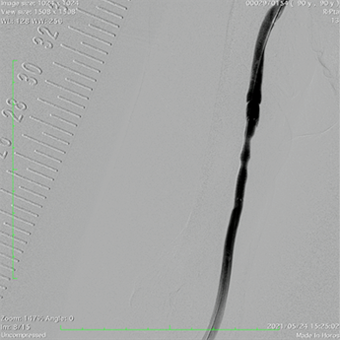

人工血管静脈吻合部狭窄にて頻回に標準のバルーン拡張(PTA)を繰り返していましたが、ステントグラフト(ゴア社バイアバーン)留置にて狭窄消失しました。

狭窄は消失